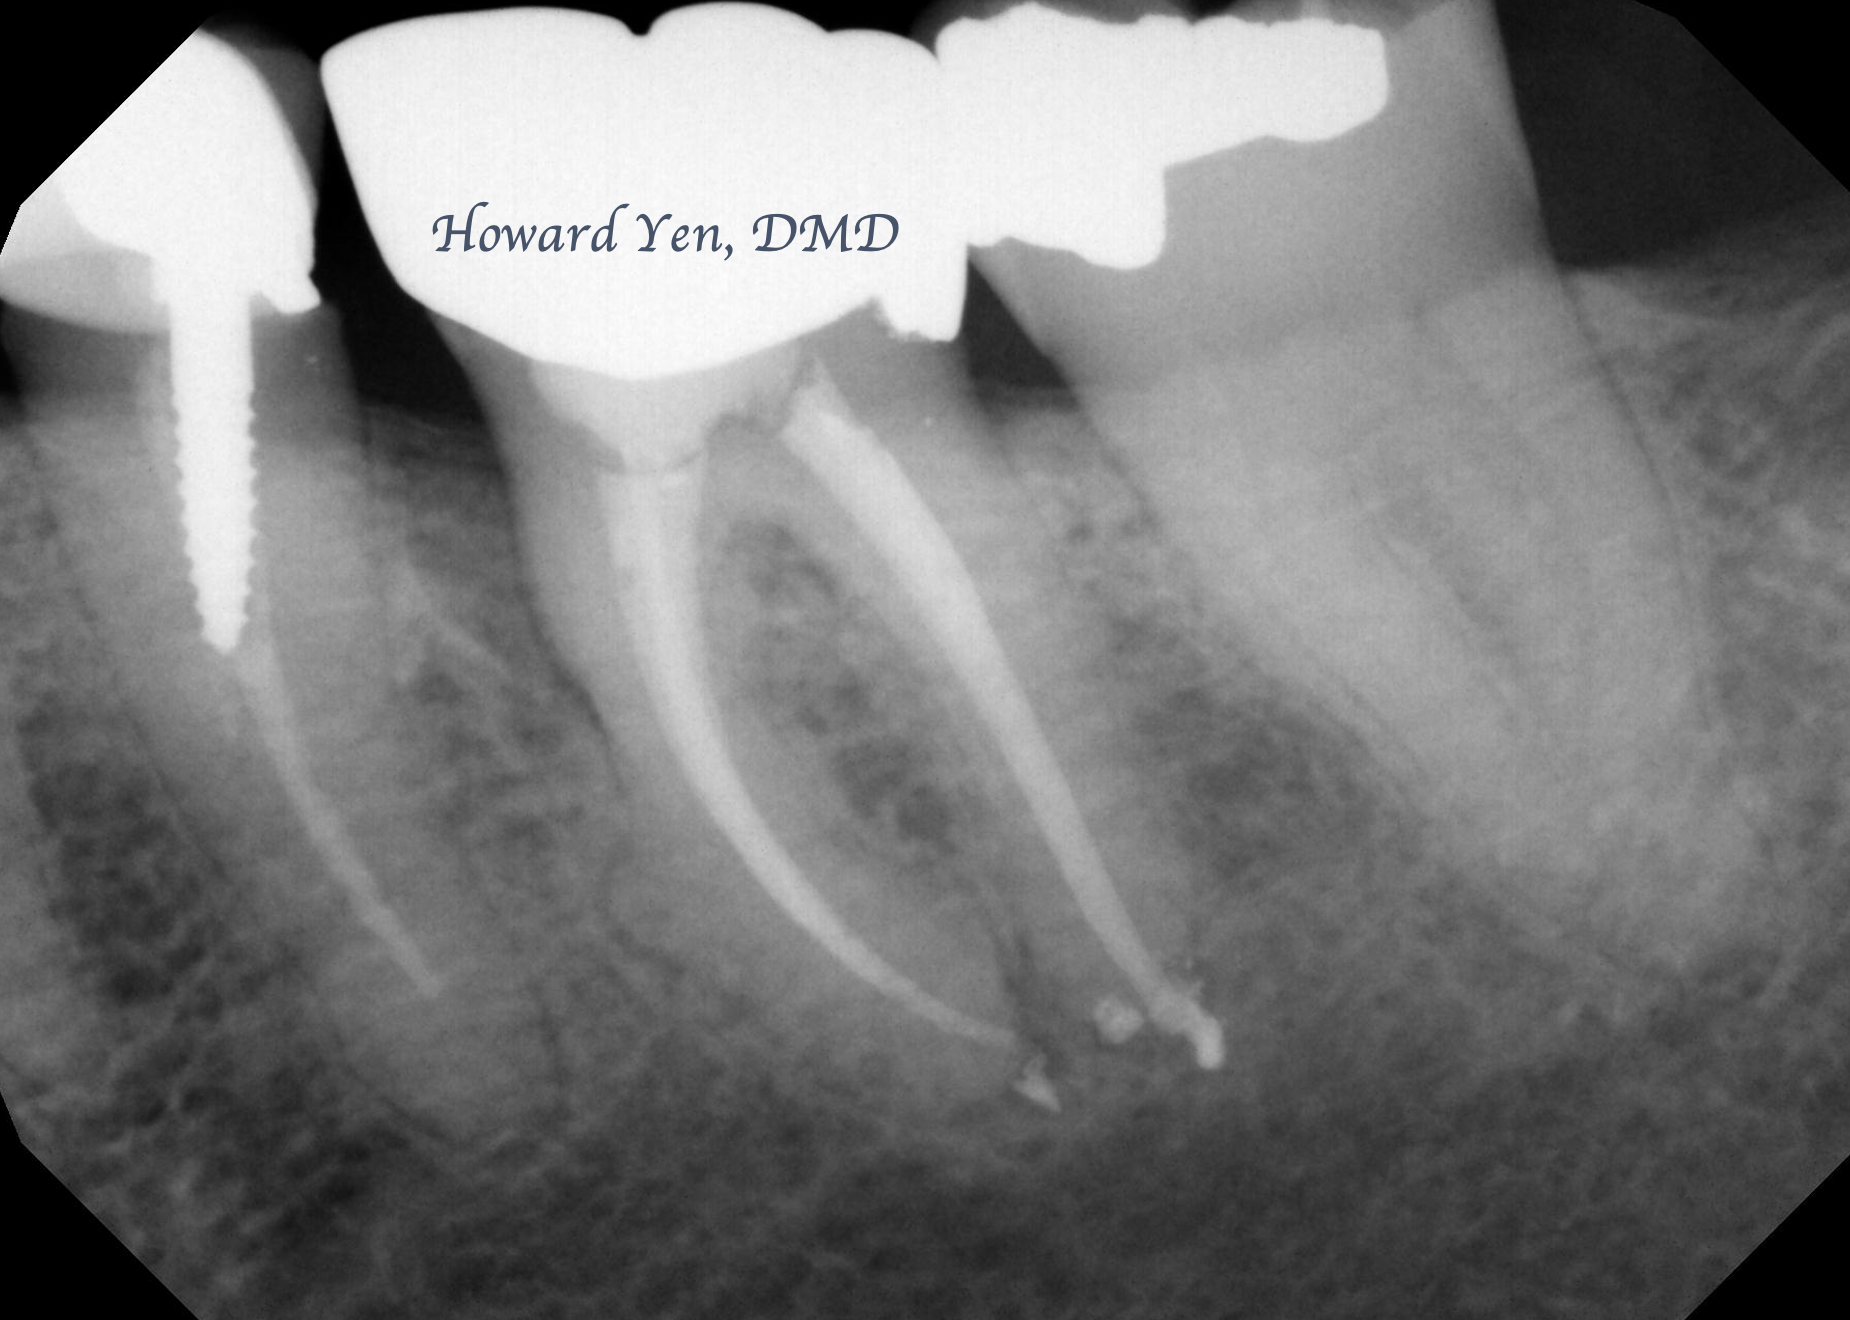

Root Amputation

Root amputation is a surgical procedure to remove diseased/fractured root of a molar in an attempt to further salvage the tooth (crown). The procedure is often done in collaboration with Endodontist (Root Canal Specialist). This is one of the classic conservative treatment option prior to the advent of modern dental implants. With proper case selection, this treatment modality is still an excellent option in preserving natural tooth.